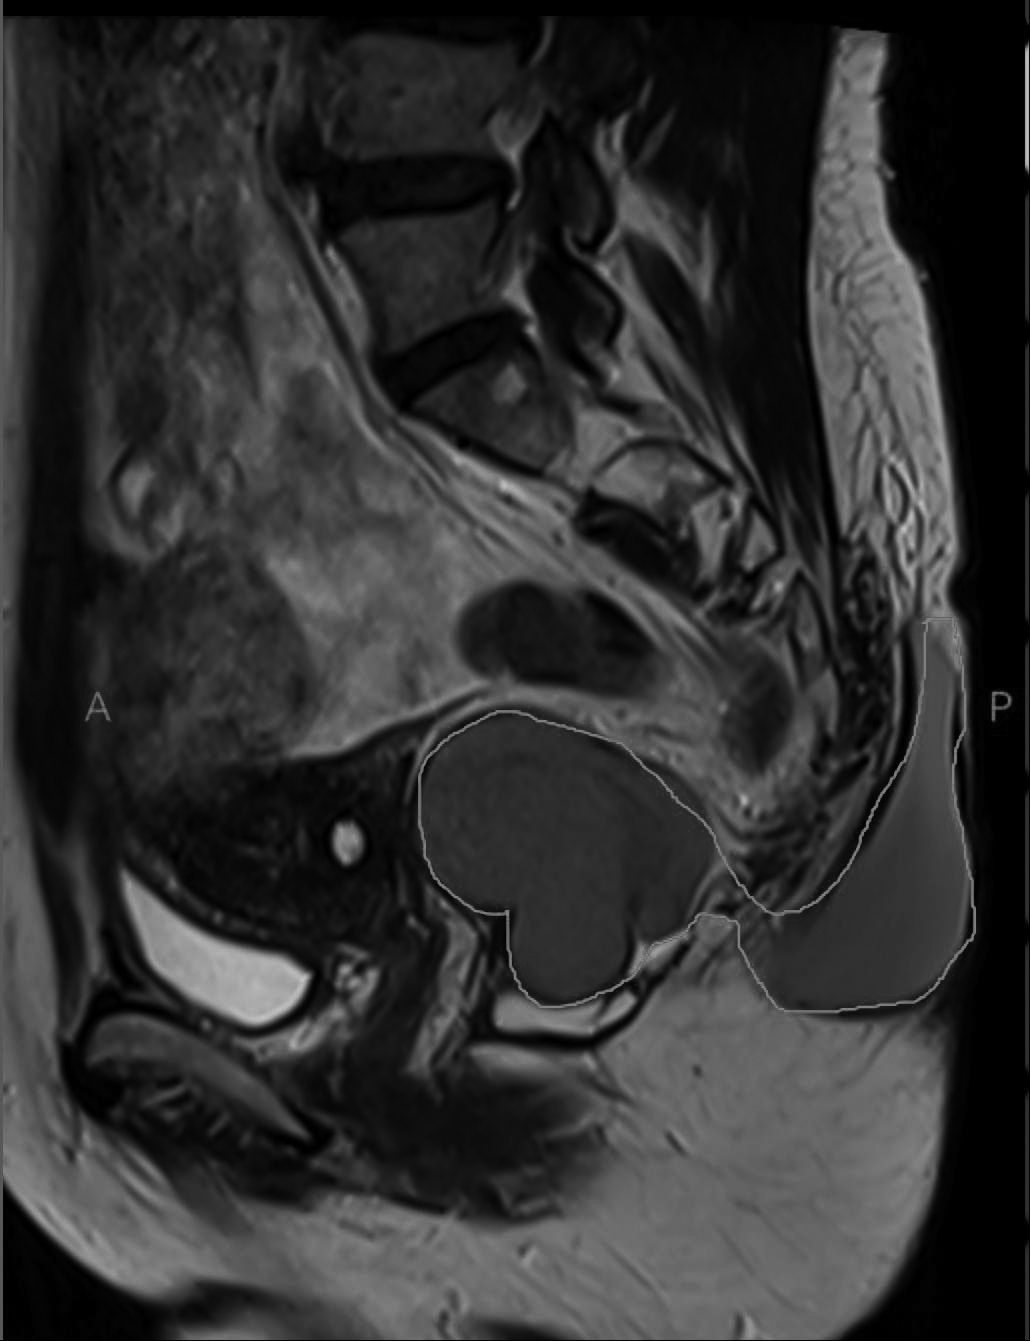

近日,40多岁的王女士来到郑州市中心医院,找我就诊。几年前,她无意中发现骶尾部有一个小包块,软软的,像小枣一样大小,不痛不痒。她在当地医院找医生看了看,医生说是一个小囊肿,良性病变,没多大问题,她也就没放在心上。 就这样一天天过去了,这个包块也一天天大了起来,王女士在平躺的时候已经感到轻微疼痛。她到医院做彩超检查,结果提示是一个边界清晰的囊性包块,外科医生建议她做一个简单的小手术。王女士找到我,希望我给她做这个手术。 在门诊为患者检查的时候,我发现这个包块位于骶尾部,也就是我们平常说的尾巴骨的地方,与周围分界清晰,局部没有红肿,肿块按起来软软的,有轻微疼痛,患者可以忍受。感觉这个包块太大,担心与肛门有关系,我建议患者住院治疗,先做个磁共振检查明确诊断,再说手术的事儿。 患者做完磁共振检查后,看着片子,我暗暗庆幸,还好当时没有在门诊给她手术,否则很难“收场”。 磁共振检查结果提示,这个包块有两部分,像一个亚腰葫芦,肚子里面一半,外面一半。外面的那一半像是从尾巴骨里面挤出来的一样,与肛门周围的肌肉和直肠的关系非常密切,如果手术,就不是一个简单的门诊囊肿切除小手术。这是一个非常特殊的骶前发育性囊肿。 我对患者说,骶前囊肿多见于她这个年龄的女性,因为囊肿位置比较深,又常常没有症状,所以早期很难诊断,等到囊肿非常大的时候,有些患者会出现肛门周围坠胀或者疼痛,并发感染的会出现发热、脓肿破溃、窦道形成等,像她这样类似亚腰葫芦的比较少见。她是幸运的,如果不是外面的这个囊肿,可能还不会被发现肚子里面的那一部分。 骶前囊肿虽然是一个良性疾病,但是要积极地进行手术治疗,这是因为骶前囊肿本身有一定的恶变概率,囊肿本身无自愈可能。随着囊肿的增大,容易继发感染,导致囊肿与盆底的肌肉和直肠分界不清晰,术中容易发生损伤,将大大增加手术的难度。很多医生在手术过程中因为担心损伤直肠和肛门括约肌,出现肠瘘和肛门失禁,术中未能将囊肿壁完整切除,导致术后复发和感染,伤口长期不愈合,给患者带来很大的痛苦。因此,术中完整地切除囊肿壁至关重要,同时还要尽可能保护肛门周围的结构和直肠,避免出现损伤。最后,我为患者完整地切除了骶前囊肿,因为准备充分,术中很好地保护了患者的直肠和肛门周围的肌肉。患者术后恢复得非常好。 (作者供职于郑州市中心医院)